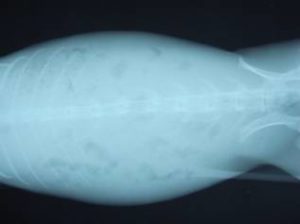

ウサギが「腸管うっ滞」をおこすと元気がなくなったり、食欲が低下したり、下痢をしたりします。

これは腸内の細菌叢に異変が起こった結果、腸内に毒素が発生して、腸毒素血症にいたる病気です。

上手に治療すれば、治りますが、この毒素が全身に回って組織壊死を起こすと死に至ります。

治療として、強制給餌や消化機能改善薬やマッサージや点滴や腸管内のガスの吸引等を行います。

原因で一番多いのは毛玉による「胃毛球症」です。